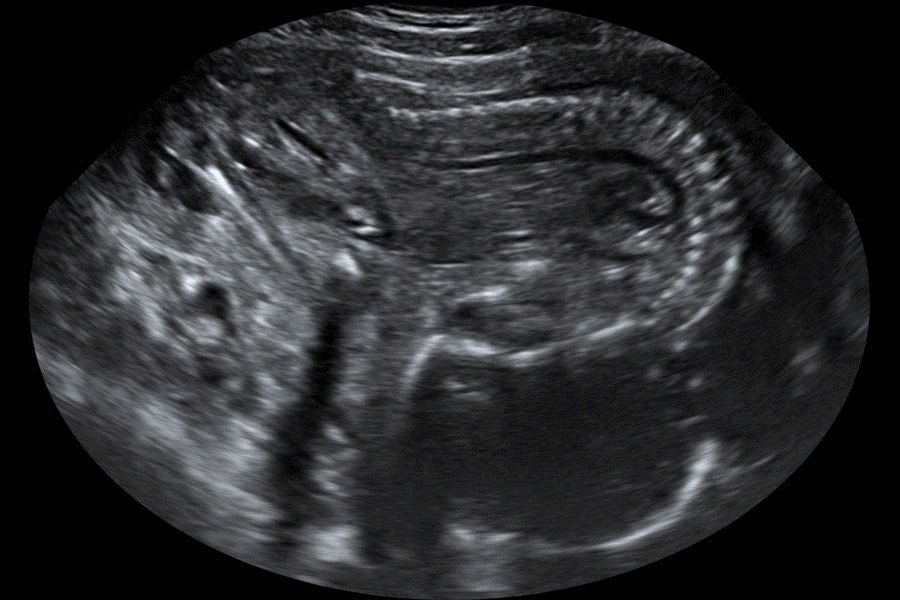

Rupture prématurée des membranes à 19 SA - Signes échographiques d'un anamnios

Images échographiques montrant un anamnios à 19 SA ; conséquence d'une rupture prématurée des membranes survenant 36 heures auparavant.

L'image échographique montre l'absence totale de liquide amniotique et avec le repli du rachis fœtal sous le fait de la constriction de l'utérus.

Les autres images échographiques montrent également, dans le présent cas : le repli du placenta ; les deux reins qui sont normaux et la vessie bien individualisable.